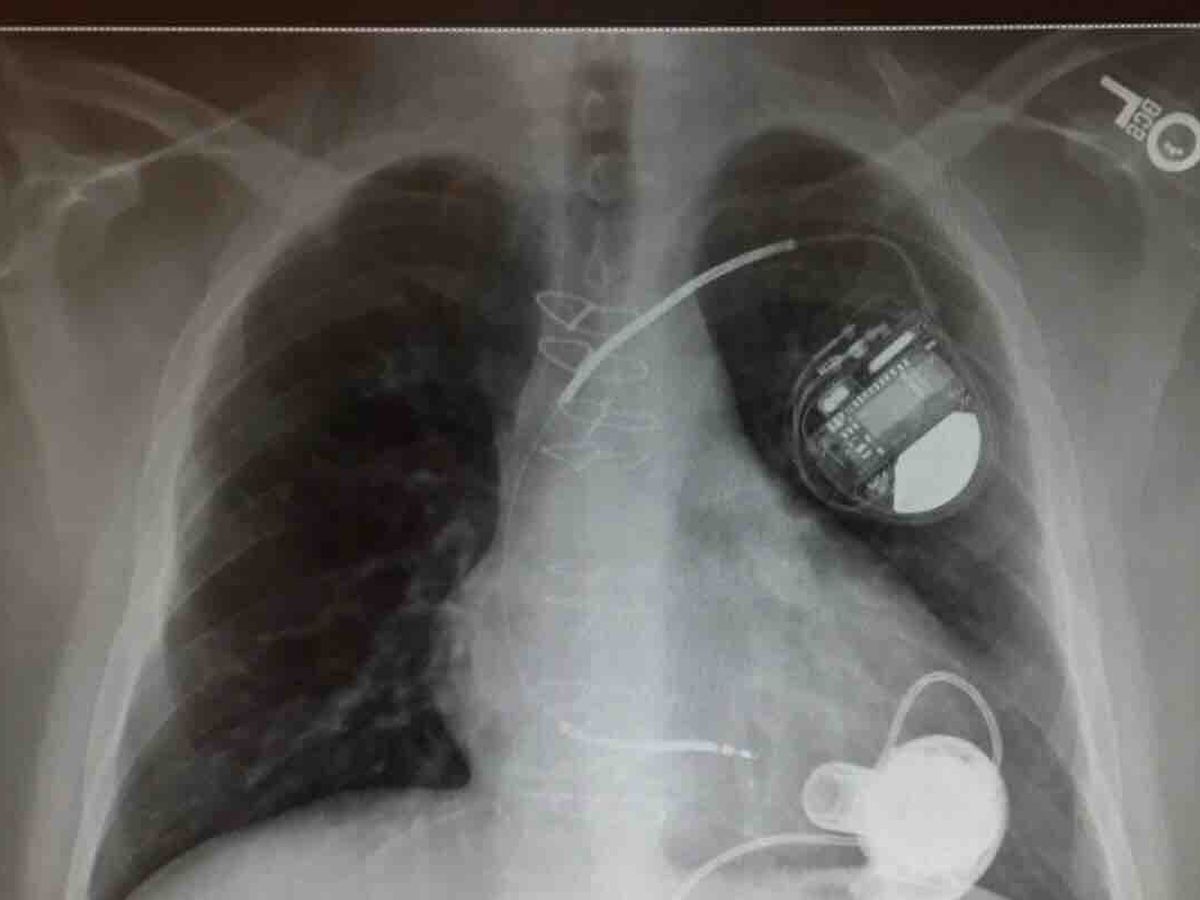

Hi everyone I trying to get some help with medical bills. I have a lot of cost due to getting my life saving heart transplant I can’t work and having to stay away from home for two months as well get my home cleaned from top to bottom because of the medication I am on to suppress my immune system. I live to far they won’t let me go home yet anyway. But having to have duct cleaned carpets and flooring and all furniture cleaned and mattresses covered ect we all know how little ssd is every month I have it spent first night trying to pay bills off. Honestly I got 2.04 in my bank account. And even if you can’t donate please share maybe someone will see anything helps god bless everyone who helps we all have struggles and I always been there to help others . Thank you for reading this